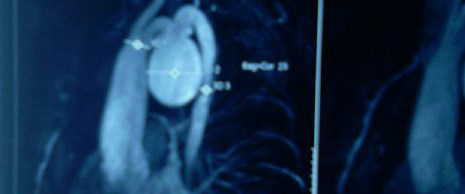

Abdominal Aort Anevrizmasi Tedavisi